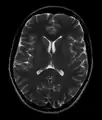

This axial T2-weighted (CSF white) MR scan shows a normal brain at the level of the lateral ventricles.

• T2-weighted (T2W) images: CSF is light, but fat (and thus white matter) is darker than with T1. T2-weighted images are useful for visualizing pathology.[26]